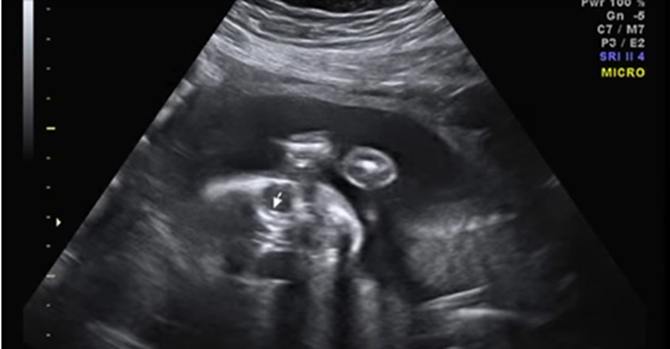

Я молюсь, чтобы ни одна мама не прошла через то, что испытала я. Я молюсь, чтобы вы разглядели любовь за тем изображением, что показывает вам ультразвук. Я молюсь, что, когда вы снова увидите ребенка с синдромом Дауна под сердцем будущей мамы, вы скажете ей правду: